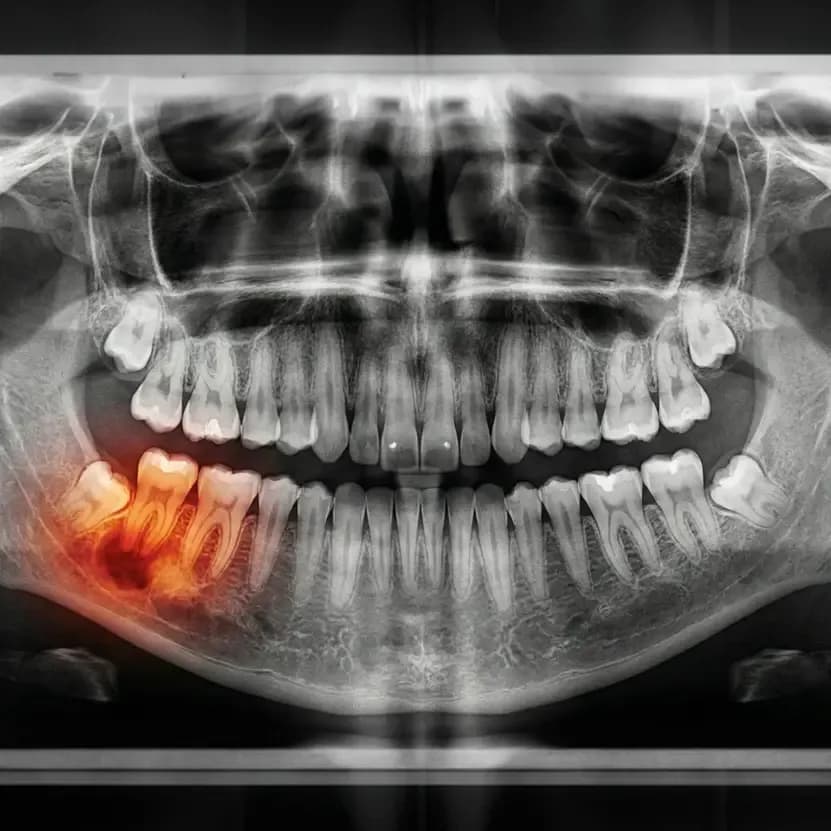

You may need a root canal if you are experiencing any of the following symptoms. The only way to confirm is a thorough examination and X-ray at one of our offices — early treatment leads to simpler procedures and better outcomes.

- Examination & Digital X-Rays We evaluate your tooth with clinical examination and digital X-rays to assess the extent of infection and confirm the diagnosis.